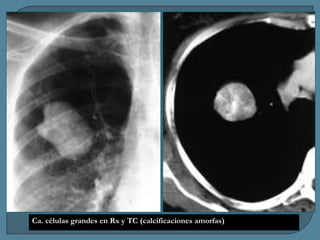

Ca. células grandes en Rx y TC (calcificaciones amorfas)